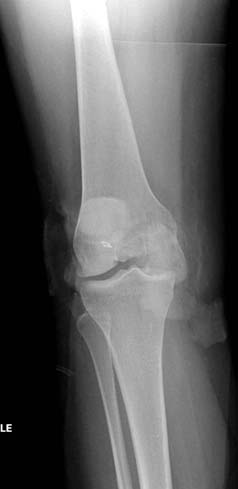

При изолированных переломах можно лечить миниинвазивно каннюлированными винтами, но в большинстве Hoffa компонент сопровождается другими типами перелома дистального бедра. Выбор доступа зависит от расположения фрагментов и большинстве латеральный субвастус доступ подойдет для фиксации перелома.

В данном случае предпочтителен парапателлярный доступ, где необходимо создать лучший обзор к мыщелку. После остеотомии и репозиции фиксацию надо проделать поперечными винтами и дополнительно задней antiglade plate - сделанной из 1/3 tubular plate.

Спасибо большое за советы! Добавляю некоторые КТ снимки. Перелом коллеги не диагностировали, видимо, расценив костную травму как повреждение задне-латерального комплекса коленного сустава. Отпишусь по результату выполненной операции.